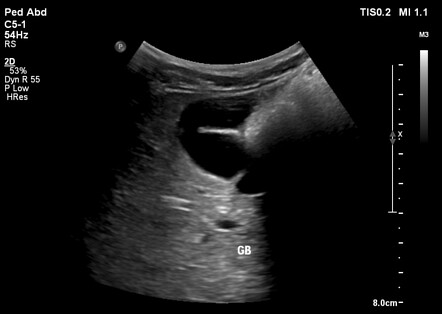

SONO: gallbladder

anechoic, pear-shaped structure

bright echogenic walls

GB wall <3 mm

measured from outer-to-outer